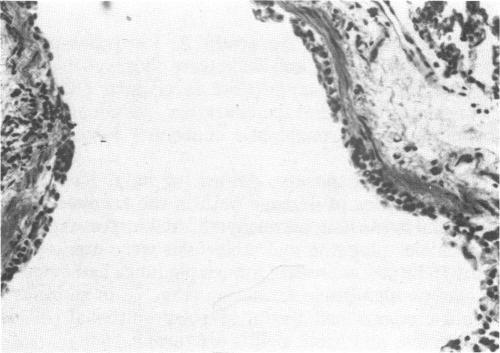

The morphologic changes induced in the lungs of rats and guinea pigs exposed to high concentrations of MIC vapor (100, 600, and 1000 ppm in the rat and 25, 125, 225, and 675 ppm in the guinea pig) for a short time (15 min) in a static exposure chamber were evaluated at varying postexposure periods (0, 1, 2, 4, and 16 hr). The 675 ppm-exposed guinea pigs were evaluated only immediately following removal from the chamber. Attention was primarily focused on the intrapulmonary conducting airways and the parenchyma (gas exchange region) of the lungs. The severity of morphologic changes observed by light microscopy was directly correlated with exposure concentration and time postexposure in both species. Specifically, degenerative changes were observed in the bronchial, bronchiolar, and alveolar epithelium in both species. Quantitative differences were observed; 100 ppm of MIC in the rat resulted in much less damage than did 125 ppm of MIC in the guinea pig. Morphologic evidence of sloughing of large sheets of conducting airway epithelium with fibrin buildup and increased mucus production resulted in plugging of major airways and atelectasis. These observations support the hypothesis that tissue hypoxia was a major contributing factor resulting in death.